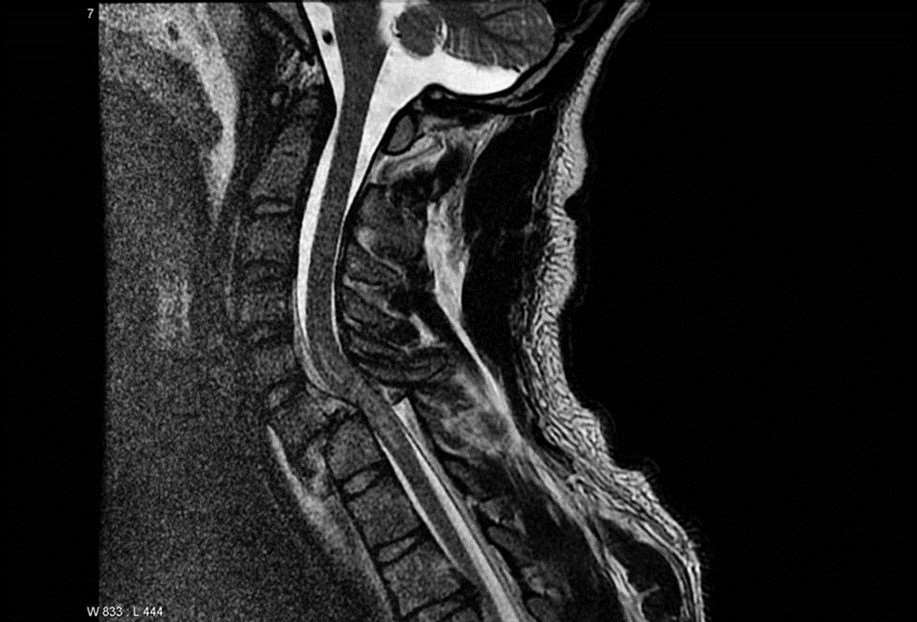

Spinal Cord Injury research at the Medical College of Wisconsin and the Clement J. Zablocki VA Medical Center include novel MRI techniques, basic science investigations, and investigational drugs and devices intended to improve the care and outcome of patients affected by spinal cord injuries. Each of our labs contribute to the understanding of the pathology and biology of SCI with active, targeted investigations in a variety of disciplines and practices. The collective objective of our research is to translate laboratory and clinical research findings into the clinical setting to improve the recovery and the quality of life for patients affected by acute and chronic SCI.

The Budde Lab is focused on developing and employing magnetic resonance imaging (MRI) as a tool to understand spinal cord biology and pathology.